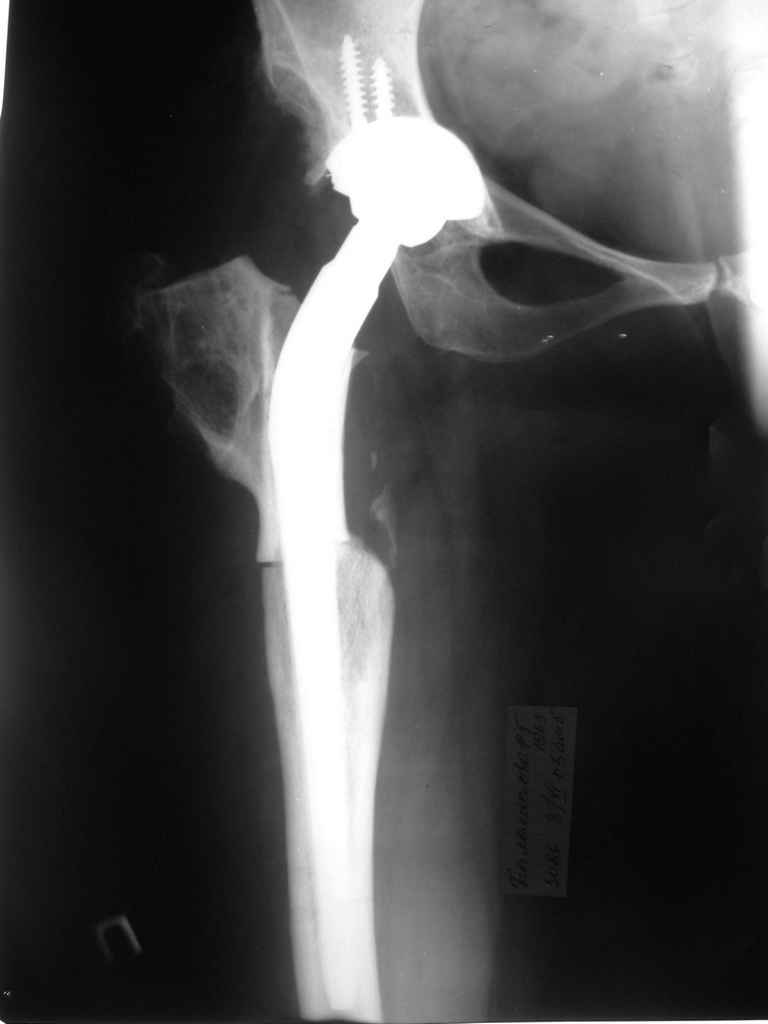

Поднят очень интересный вопрос об эффективности создания опорного бедра по Илизарову у молодых пациентов (ок). Наверное мне не повезло и я не

видел положительных результатов после этих операций, а вот проблемных больных приходится видеть достаточно часто. Причем сроки их обращения

после остеотомии короткие - 3-5 лет, а выполнение эндопротезирования после остеотомии на двух уровнях с многоплоскостной деформацией является

серьезным испытанием и для пациента и для хирурга. Я тоже не сторонник эндопротезирования в молодом возрасте, но уж после неудачных остеотомий

остеотомии. Я представил Р-граммы больных с неудачными р-ми после остеотомий.

Эндопротезирование у них было на порядок сложнее в отличие от артропластики без проведения остеотомии.